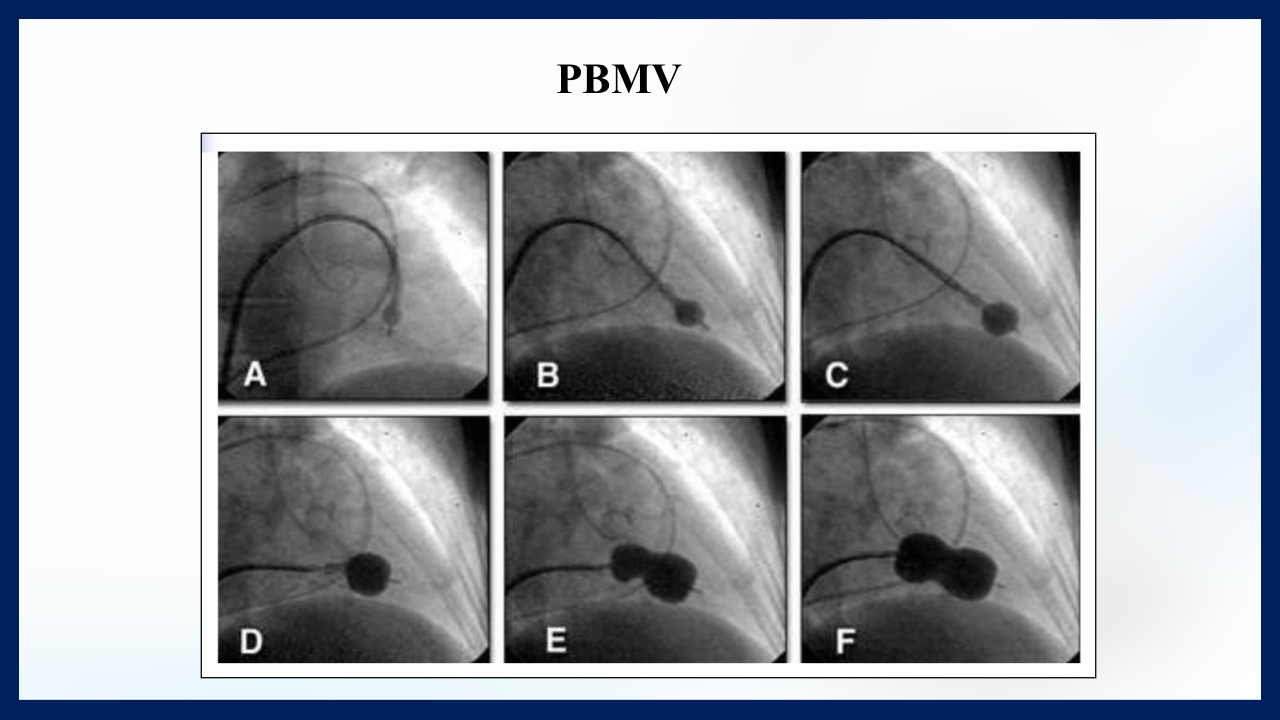

心 脏 瓣膜 医师:XXX 日期:20XX.XX.XX 讲授目的和要求 1 掌握二尖瓣和主动脉瓣膜病变的病理生理、临床表现及诊断方法。 熟悉二尖瓣和主动脉瓣膜病变的病因、鉴别诊断、并发症、治疗原则及 2 手术适应证。 3 了解瓣膜病的检查方法及治疗新进展。 心脏瓣膜病 是由于炎症、粘液样变性、退行性改变等原 因引起的单个或多个瓣膜结构的功能或结构异常,导致 瓣口狭窄及(或)关闭不全。二尖瓣最常受累,其次为 主动脉瓣。 (Rheumatic Heart Disease)简称风心病, 是风湿性炎症过程所致瓣膜损害,主要累及40岁以下人 群。 瓣膜粘液样变性和老年瓣膜钙化所致瓣膜病日渐增多。 3 瓣膜病分类 按病因分类: 风湿性、老年退行性、先天性、相对性 按受累部位和类型分: 二尖瓣狭窄、二尖瓣关闭...